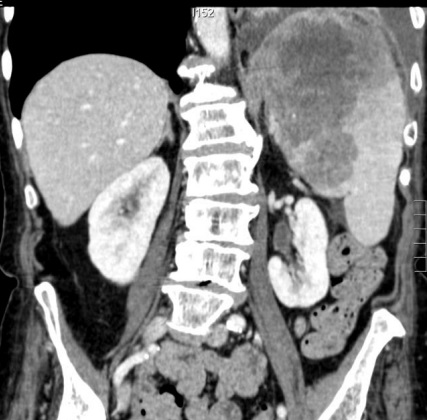

Image radiologique TDM en coupe coronal de

adenopathie peripherique , peri-splenique ,

peri-coeliacque ou mesenterique d'une lymphome maligne de la rate peu être s'observer |